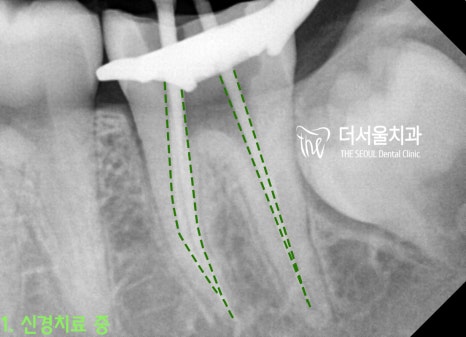

* 치아교정 전

#37번 큰 어금니에 충치가 있던 관계로

인비절라인을 마무리하면서

신경치료 및 크라운을 씌워드렸습니다.*